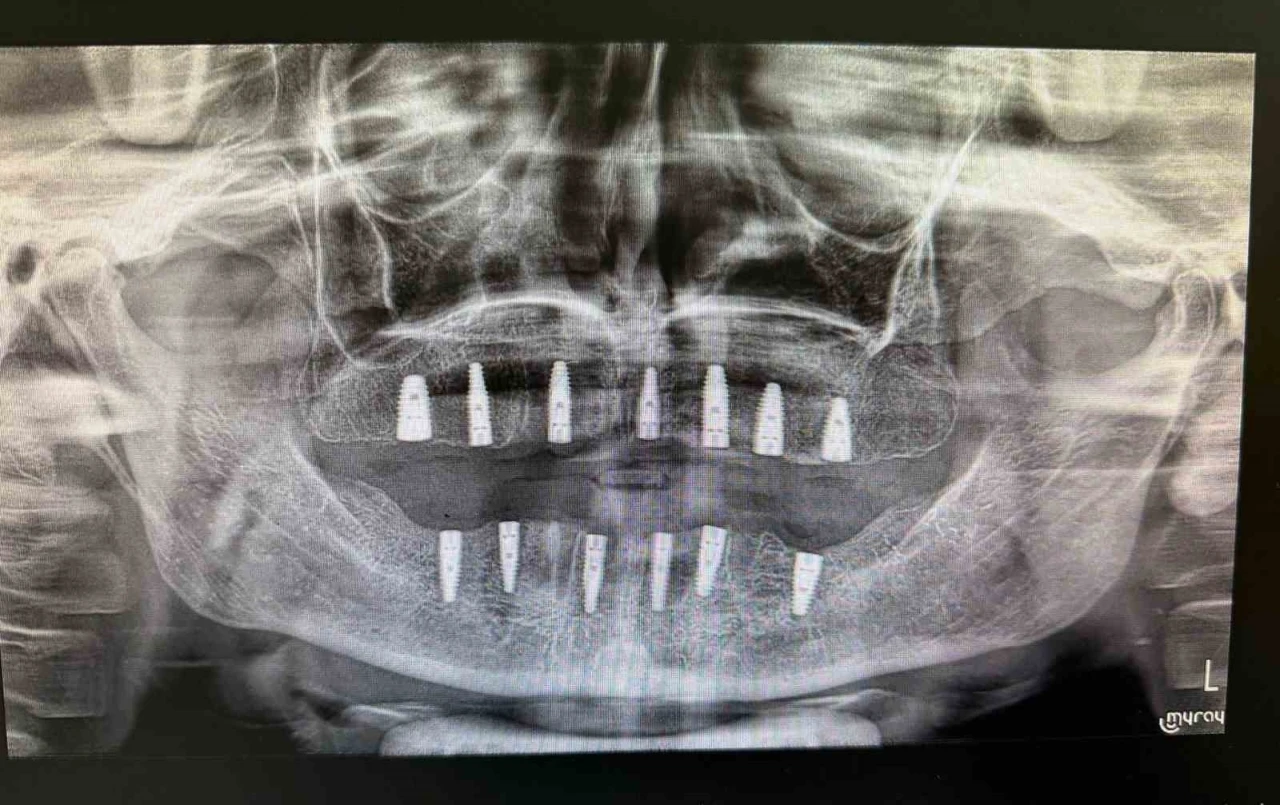

Bayburt Ağız ve Diş Sağlığı Merkezinde tamamen dişleri olmayan bir hastaya implant tedavisi uygulandı. Tedavi sonrası hasta, yeni dişlerine kavuştu.

Merkezde görevli Uzm. Dt. Sefa Merve Arıkan tarafından gerçekleştirilen ameliyatta hastaya 13 adet implant yerleştirildi.